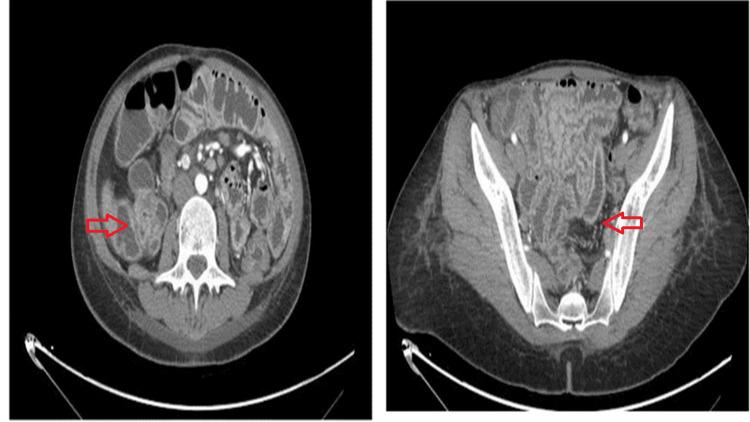

Autoimmune enteropathy (AIE) is a differential diagnosis of incurable chronic diarrhea, malnutrition, and weight loss. This type of diarrhea is associated with protein enteropathy that usually affects the small intestine. The diagnosis of AIE is based on chronic diarrhea, malabsorption, specific histological result, antibodies against enterocytes, and excluding similar conditions. In this case, a 28-year-old female presented with diarrhea, lower limb edema, weight loss, and electrolyte imbalances. Endoscopic examination demonstrated duodenal villous atrophy, while duodenal biopsies revealed villous blunting, scattered intraepithelial lymphocytes, and crypt hyperplasia in the lamina propria. The patient was treated with immunosuppressive treatment including methylprednisolone and azathioprine, achieving clinical remission.

自身免疫性肠病(AIE)是一种难以治愈的慢性腹泻、营养不良和体重减轻的鉴别诊断疾病。这种类型的腹泻与通常影响小肠的蛋白质肠病有关。AIE的诊断基于慢性腹泻、吸收不良、特定的组织学结果、抗肠上皮细胞抗体以及排除类似病症。在本病例中,一名28岁女性出现腹泻、下肢水肿、体重减轻和电解质失衡。内镜检查显示十二指肠绒毛萎缩,而十二指肠活检显示绒毛变钝、固有层散在的上皮内淋巴细胞以及隐窝增生。该患者接受了包括甲泼尼龙和硫唑嘌呤在内的免疫抑制治疗,实现了临床缓解。